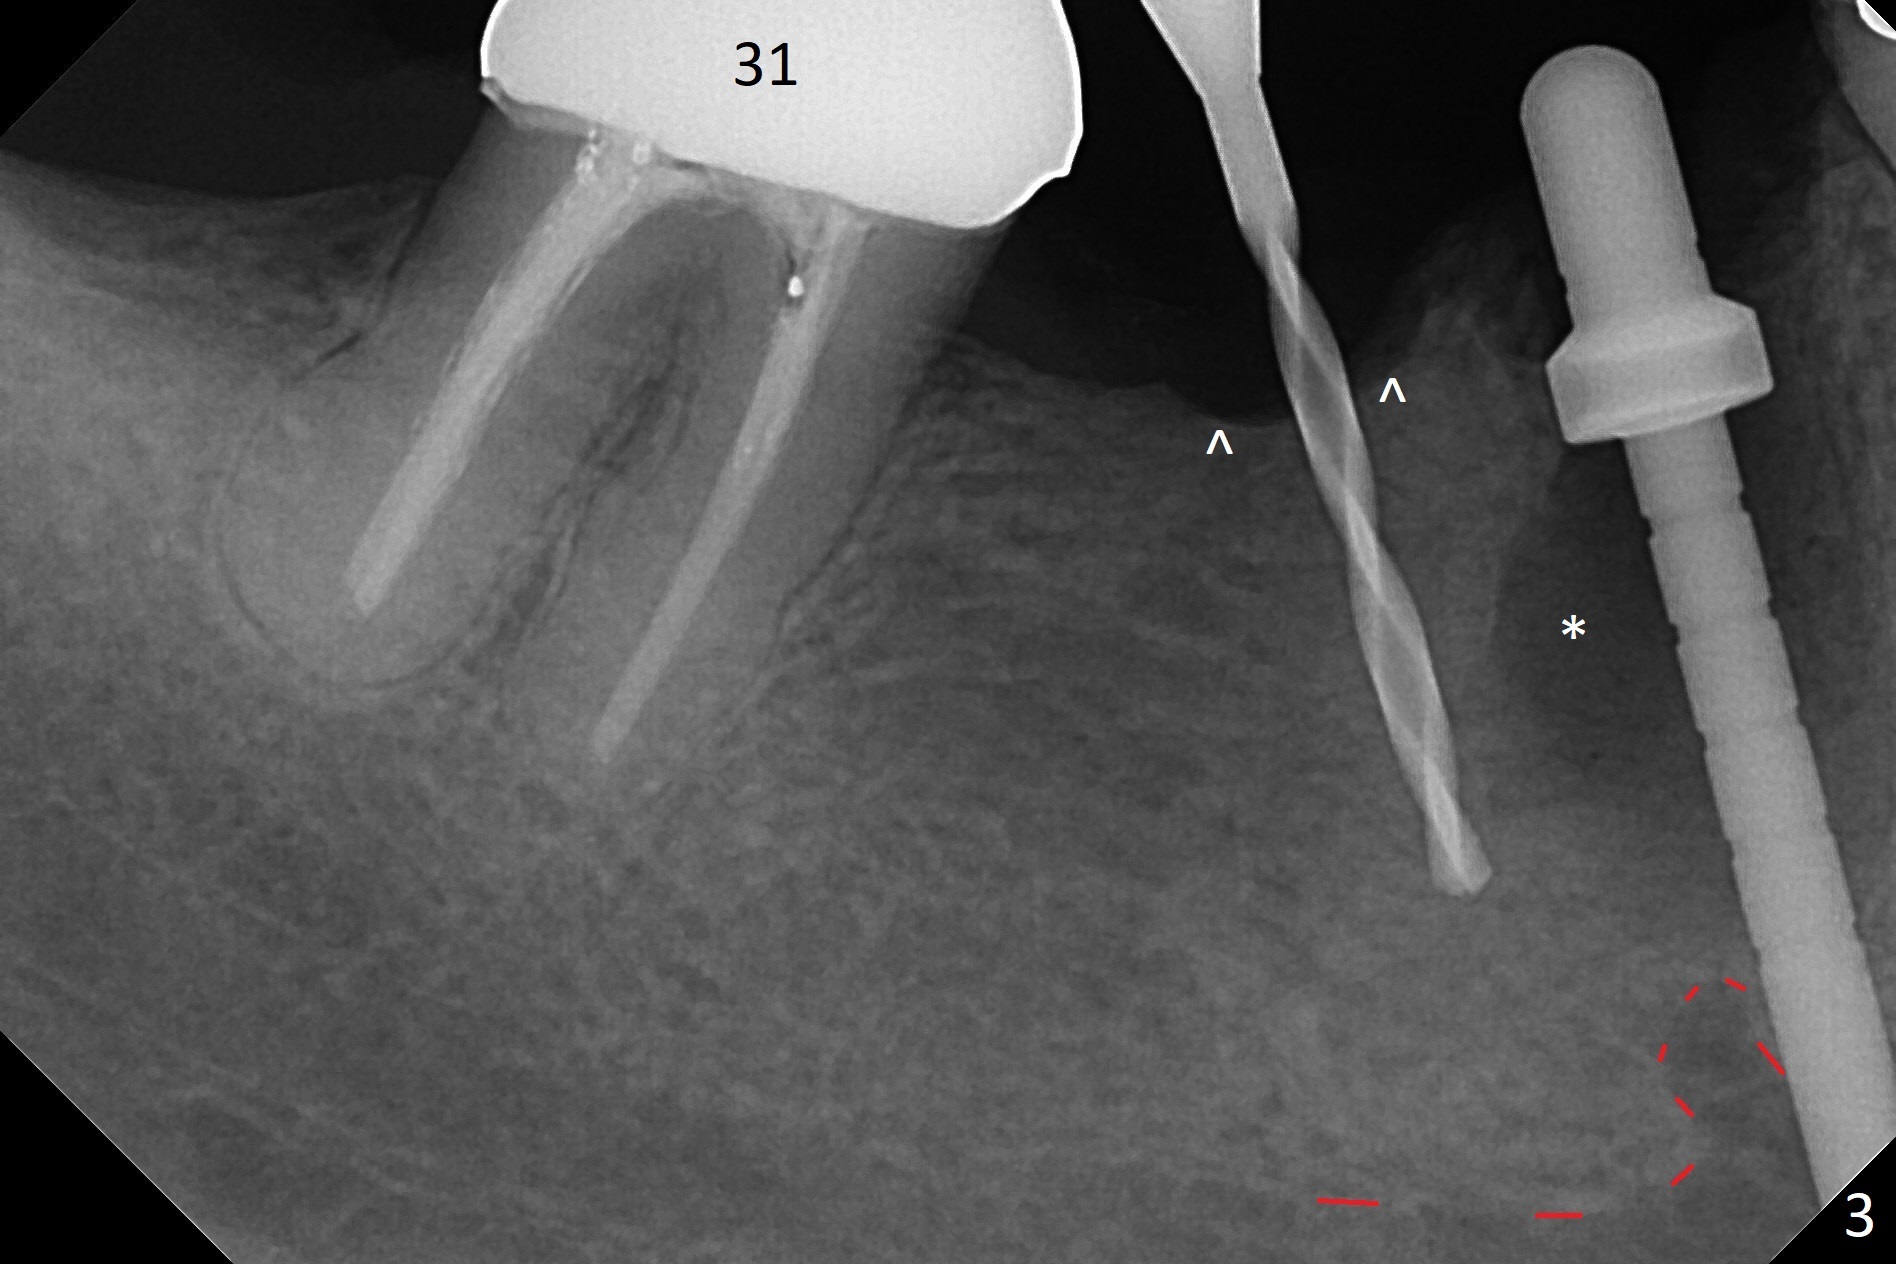

Preop examination shows that the buccal plate at #30 is atrophic (Fig.1 *). The mesiodistal width of the pontic is narrow as compared to the retainer at #31 (Fig.2). It appears that a narrow implant should be placed at #30 and should be able to sustain functional loading. After ridge reduction at #30 (Fig.3 ^) and extraction and debridement at #29, osteotomies at these sites are initiated with 1.2 mm and 2 mm drills, respectively. Probably due to low bone density, the osteotomy at #29 drops deep and close the Mental Loop (red dashed line). While the trajectory at #30 improves, the osteotomy at #29 remains close to the Mental Loop (Fig.4), asymptomatic with infiltration anesthesia. A 3x12(2) mm 1-piece implant is placed at #30 and 3.8x16 mm 2-piece implant at #29 (Fig.5,6 with insertion torque >50 and <50 Ncm, respectively). The large distal defect at #29 (Fig.3,5 *, most likely due to post-related perforation) is later filled with bone graft (data not shown). After placing an abutment at #29 and suturing, periodontal dressing is applied. Three months later, the meisal gap of #29 disappears while the distal one reduces (Fig.7 *). The abutment is changed to 4.5x4(4) mm one before reprep for impression. There is no bone loss 9 months post cementation (Fig.8) or 3 years 9 months post cementation (Fig.9). In fact the crown is lost at #31. At repeated request from the patient, a prefabricated post and crown will be fabricated for short term purpose while an implant is going to be placed at #19. The new crown at #31 has no occlusal contact (Fig.10), which may change over time.